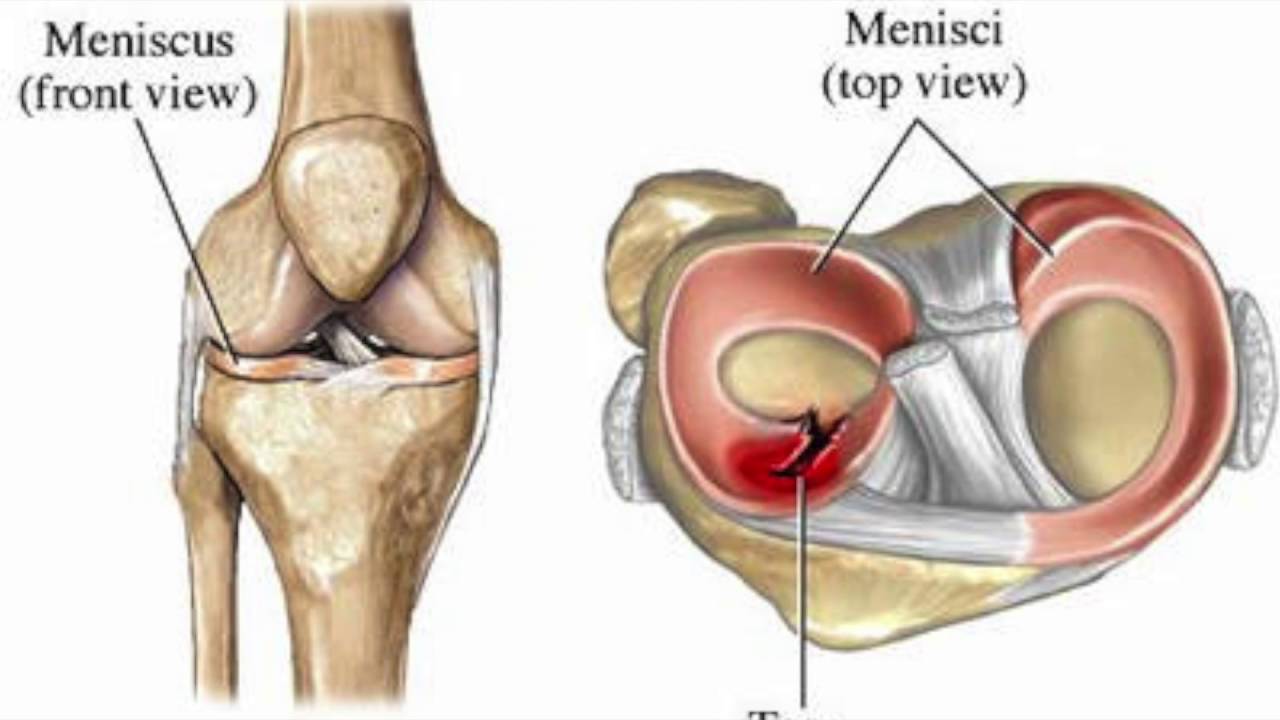

Анатомия коленного сустава: изучение анзерита и его влияния